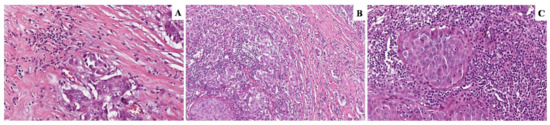

2.2. Histological Evaluation of TILs

3.1. Patient’s Characteristics and TILs Distribution